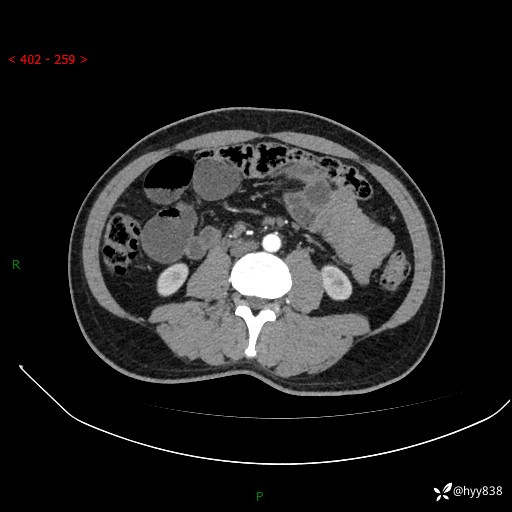

年轻男性,腹痛5月余。除了肠梗阻,你还能看到什么---结果公布~

主诉:腹痛5月余。

现病史:患者于5月前无明显诱因开始出现腹痛,上明显,为间断性胀痛不适,无畏寒发热,无心慌气促等特殊不适,遂来我院。我院门诊遂以“腹痛原因待查”收入我科。 起病以来,患者精神、饮食、睡眠欠佳,大小便正常。体力体重无明显变化。

腹部CT增强扫描(动脉期+静脉期)